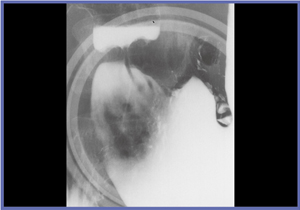

きれいに写るものも,きれいに写そうとしなければ写らないのであり,技師は良い画像を撮ることを意識しなければならない。バリウムをきれいに付着させる(図4),Cアームを活用して病変を正面からとらえる(図5)といったことにきちんと取り組むことが重要である。

![]() 図5 アーム回転による病変観察 |